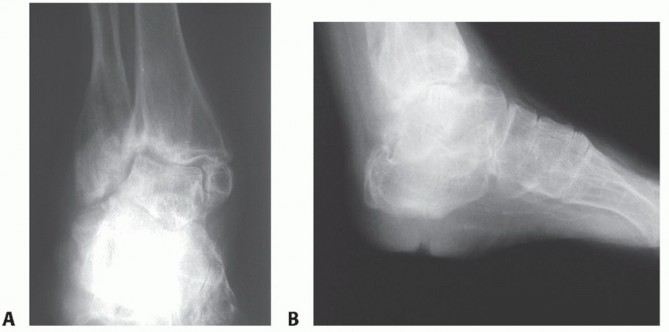

DEFINITION Tibiotalocalcaneal arthritis is formally defined as the loss of cartilage from both the tibiotalar…